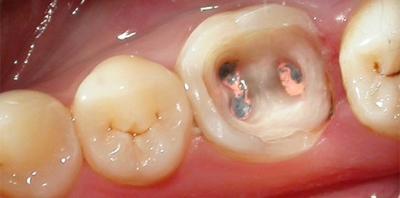

Пустоты в корне зуба после пломбирования

Пломба должна плотно закрывать каналы, но если процедура проведена некачественно, после затвердевания лекарственного вещества остаются пустые зоны в корне зуба.

Пломбирование проходит, как правило, в три этапа: удаление нерва, повторная чистка каналов и установка постоянной пломбы. Поспешность и несоблюдение технологии пломбирования приводят к неприятным последствиям. Для лечения также потребуется повторно установить новую пломбу.